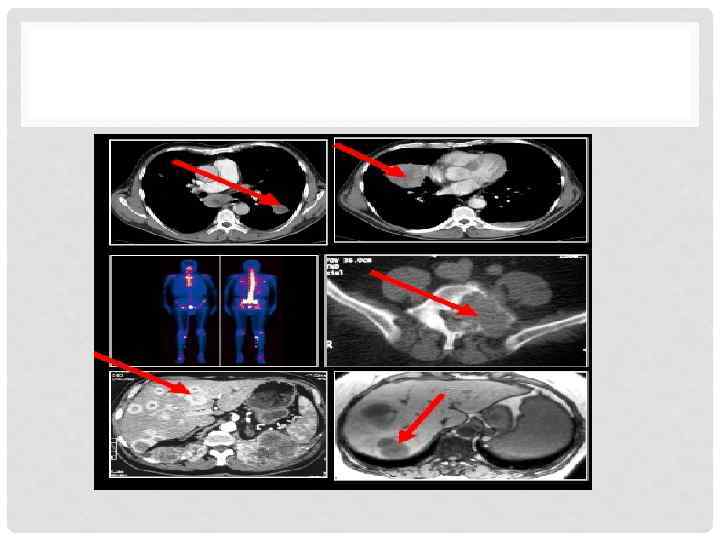

ДИАГНОСТИКА • Стандартные исследования. • Рентгенография ОГК ( большие округлые тени «пушечные ядра» ). • КТ. • МРТ. • Дуплексное УЗИ (опухолевый тромб). • Сцинтиграфия костей. • КТ головного мозга. • Чрескожная пункция (крайне редко). • Открытая биопсия или нефрэктомия.

ЛЕЧЕНИЕ • При распространении опухолевого тромба в просвет почечной или нижней полой вены выполняется удаление тромба. В случае распространения опухолевого тромба в просвет НПВ вена пережимается выше и ниже тромба, а также противоположная почечная, с последующим его извлечением после рассечения вены над тромбом. При прорастании сосудистой стенки опухолью производится резекция данного участка НПВ на всю толщину сосудистой стенки. • В случае распространения опухоли на окружающие органы и ткани производятся комбинированнные операции с резекцией пораженных органов и тканей с интраоперационным исследованием краев отсечения

ЛЕЧЕНИЕ • У первичных больных ПКР с резектабельными отдаленными метастазами и удовлетворительным общим состоянием показана радикальная или расширенная нефрэктомия с удалением метастазов, поскольку полное удаление метастатических опухолей улучшает прогноз. • У больных ПКР с множественными и/или нерезектабельными отдаленными метастазами, удовлетворительным общим состоянием и низким риском оперативного вмешательства показано проведение комплексной терапии с циторедуктивной нефрэктомией на первом этапе и последующей системной терапией. • В лечении распространенного ПКР при возможности могут применяться препараты таргетной терапии (сунитиниб, бевацизумаб с интерфероном-альфа, сорафениб).